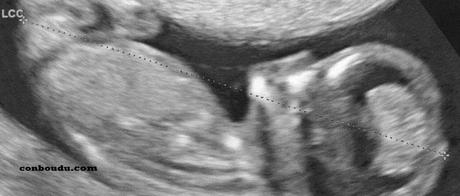

La toute 1ère écho.

La 1ère rencontre avec notre bébé.

Donc cette toute 1ère échographie, celle du 1er trimestre, celle des 12 sa que nous attendons tous est bien arrivée, et pour certains plusieurs fois.